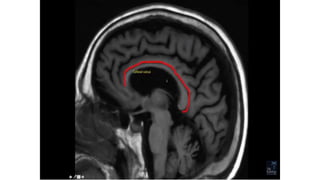

SULCI & GYRI

SULCUS IS THE DEPRESSION [VALLEYS]

AND

Fissure/sulcus Importance

• Interhemispheric fissure • Separates two lobes

 Sylvian fissure/ Lateral

Sulcus

 Frontal to temporal

 Central sulcus  Frontal to parietal

 Callosal sulcus

 Cingulate sulcus

 Interparietal sulcus

 Parieto occipital sulcus

 Calcarine sulcus

12